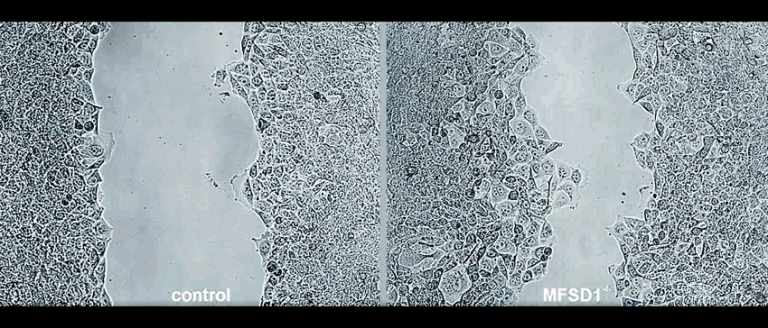

为什么一些患者会发生肿瘤转移,而另一些则不会?科学家对其中原因还不甚清楚。最近,奥地利科技学院研究人员在《肿瘤学前沿》发文指出,一种名为MFSD1的蛋白质会抑制癌细胞的转移。

MFSD1是哺乳动物中的一种蛋白质。研究小组在小鼠体内制造了缺乏这种蛋白质的癌细胞。没有这种蛋白质,癌细胞的移动速度要快得多,这表明MFSD1阻止了癌细胞的移动。研究人员在患有乳腺癌、结肠癌和皮肤癌的活小鼠身上进行了测试,结果表明,在缺乏MFSD1的情况下,转移率有很大的增加。